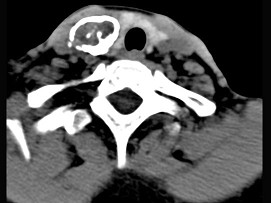

(8-10题共用题干)

20.50岁女性患者,体检发现右侧甲状腺有较硬结节,CT扫描如图所示,请选择正确的描述和答案  (    )

正确答案:ABE